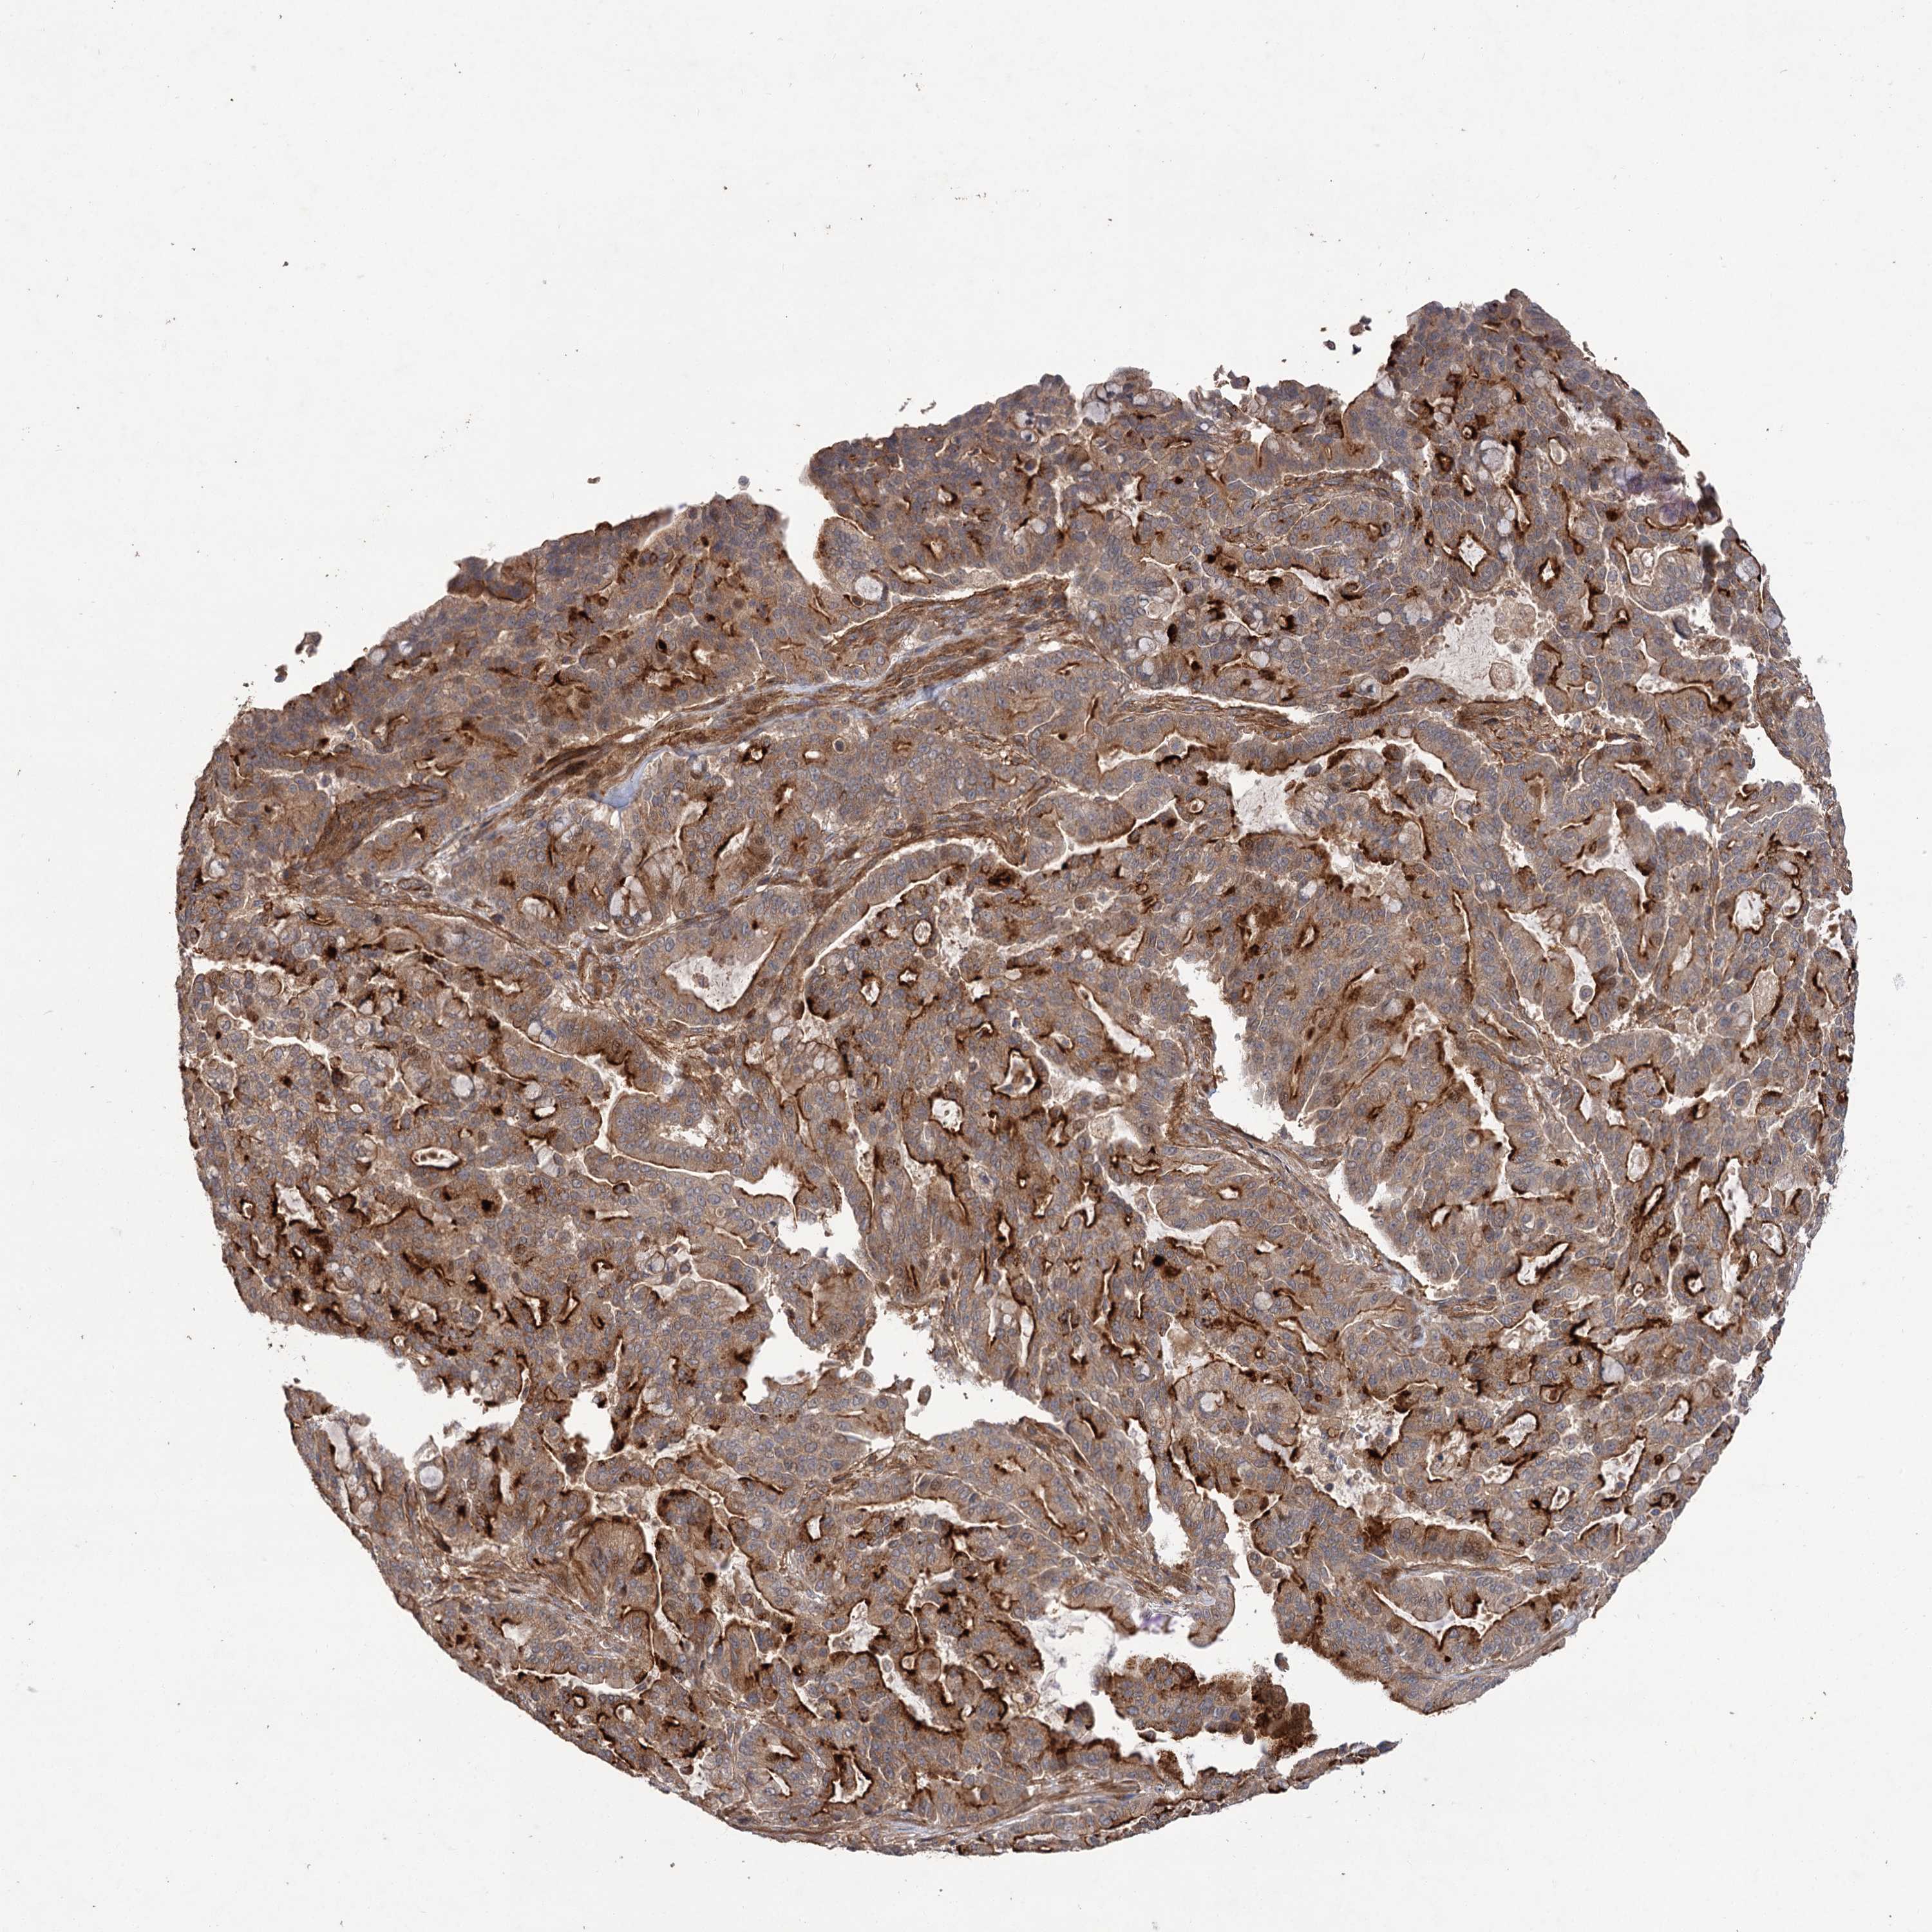

PANCREATIC CANCER - Protein expressioni

A mouse-over function shows sample information and annotation data. Click on an image to view it in a full screen mode. Samples can be filtered based on level of antibody staining by selecting one or several of the following categories: high, medium, low and not detected. The assay and annotation is described here.

Note that samples used for immunohistochemistry by the Human Protein Atlas do not correspond to samples in the TCGA dataset.

Antibody stainingi

Antibody staining in the annotated cell types in the current human tissue is reported as not detected, low, medium, or high, based on conventional immunohistochemistry profiling in selected tissues. This score is based on the combination of the staining intensity and fraction of stained cells.

Each image is clickable and will lead to virtual microscopy that enables deeper exploration of all samples and also displays staining intensity scores, fraction scores and subcellular localization as well as patient and tissue information for each sample.

Antibody HPA038850

Antibody HPA038851

Staining

High

Medium

Low

Not detected

Intensity

Strong

Moderate

Weak

Negative

Quantity

>75%

75%-25%

<25%

None

Location

Nuclear

Cytoplasmic/membranous

Cytoplasmic/membranous,nuclear

Adenocarcinoma, NOS